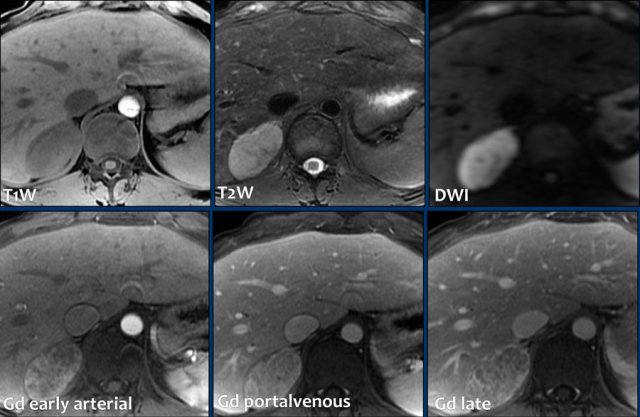

MRI-images of a 5.6 cm right adrenal carcinoma incidentally discovered on ultrasound.

Top row: mild T1W hypointensity, moderate T2W hyperintensity and intense hyperintensity on DWI.

Lower row:

Post contrast images show inhomogenous progressive enhancement with inhomogeneous progressive capsular enhancement in the portal and delayed phase.